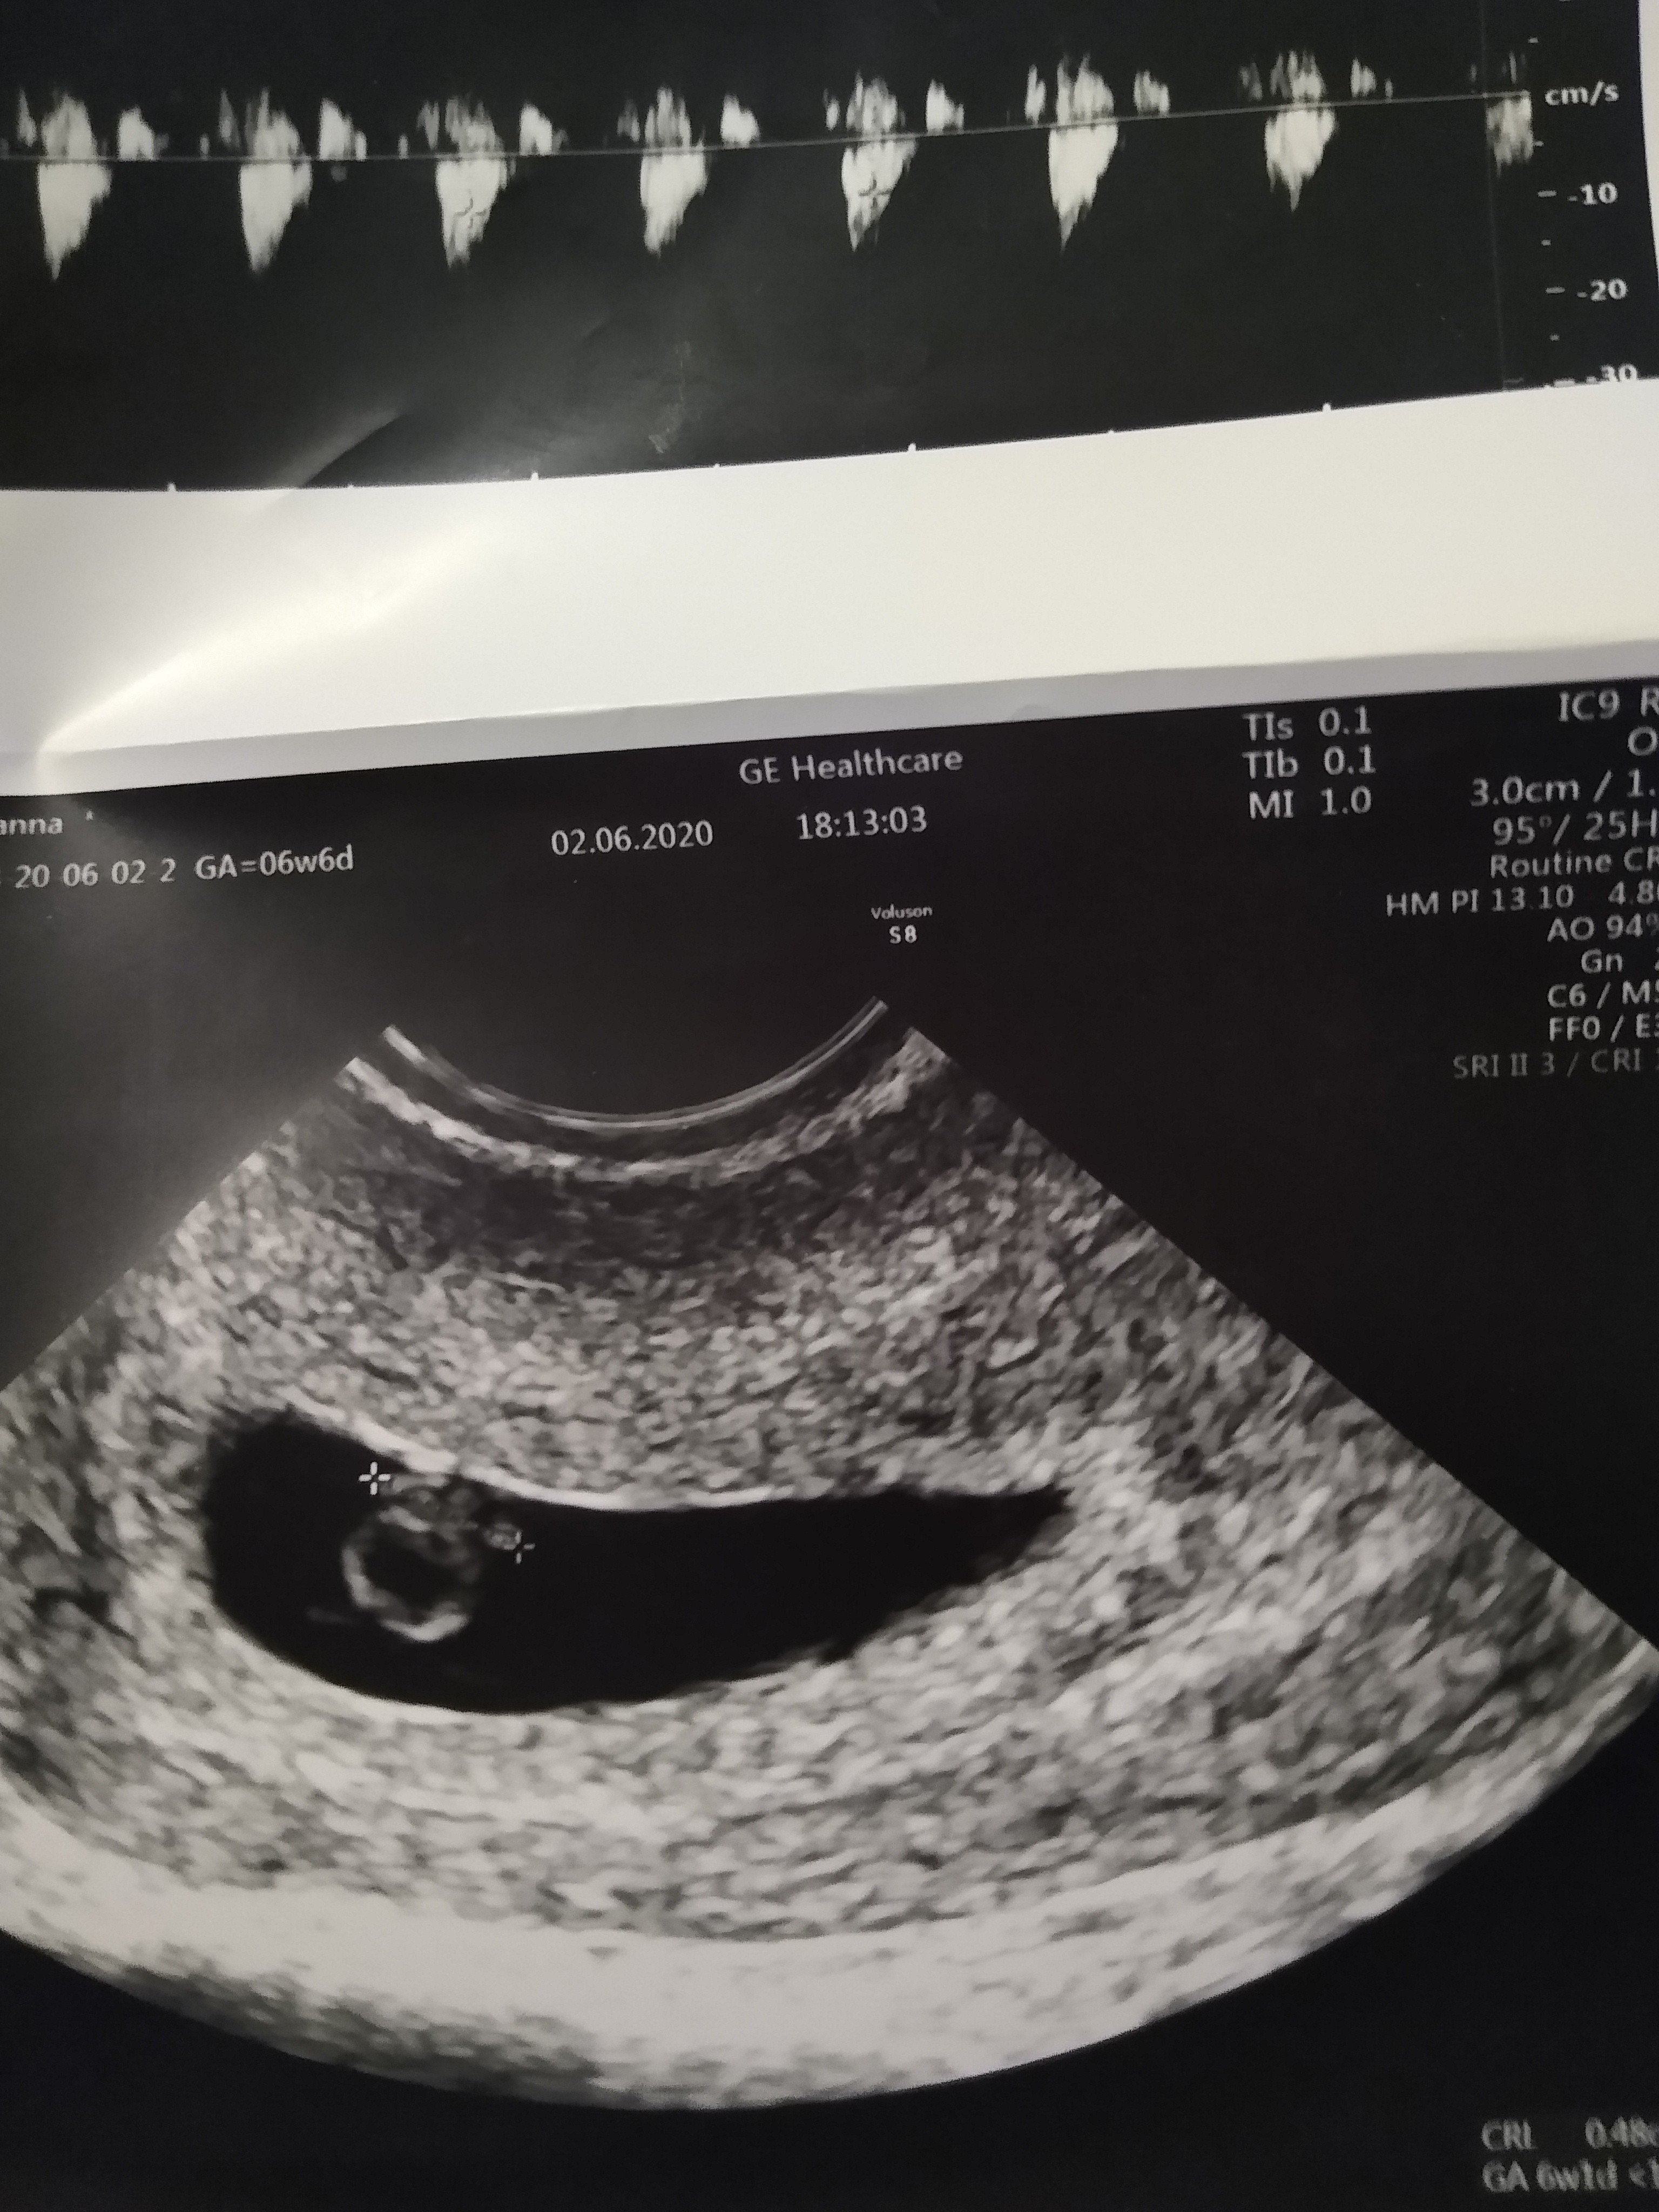

Piękne [emoji3059] Zaczynam dochodzić do wniosku, że tam gdzie chodzę jest koszmarny aparat do usg, bo moje wygląda jak burza śnieżna w porównaniu do tego [emoji85]Mam [emoji4]

A chodzisz na NFZ? Ja byłam w przychodni, ale Pani Doktor powiedziała, że sprzęt jest kiepski i wzięła mnie na oddział na badanie (w poprzedniej ciąży zobaczyła ja dopiero na USG w 8tc :O).Piękne [emoji3059] Zaczynam dochodzić do wniosku, że tam gdzie chodzę jest koszmarny aparat do usg, bo moje wygląda jak burza śnieżna w porównaniu do tego [emoji85]

Ale się fajnie ułożył, widać chyba rączki i nóżkiWysylam mojego szkraba